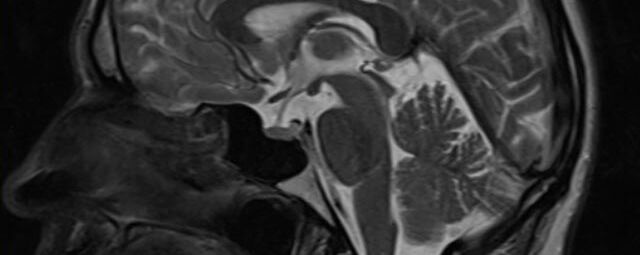

Kopf/Hals

Kopf

• akute Schlaganfalldiagnostik und chronische Durchblutungsstörungen

• entzündliche Prozesse des Gehirns oder der Gesichtsweichteile

• Tumore, ggf. mit Spektroskopie

• Abklärung Schwindel, zentrale Sehstörung, Kopfschmerz

• Metastasenverdacht

• Multiple Sklerose

• Abklärung Hirnnerven, Schädelbasis inkl. Hypophyse

• Abklärung Kleinhirn, Hirnstamm, Halsmark